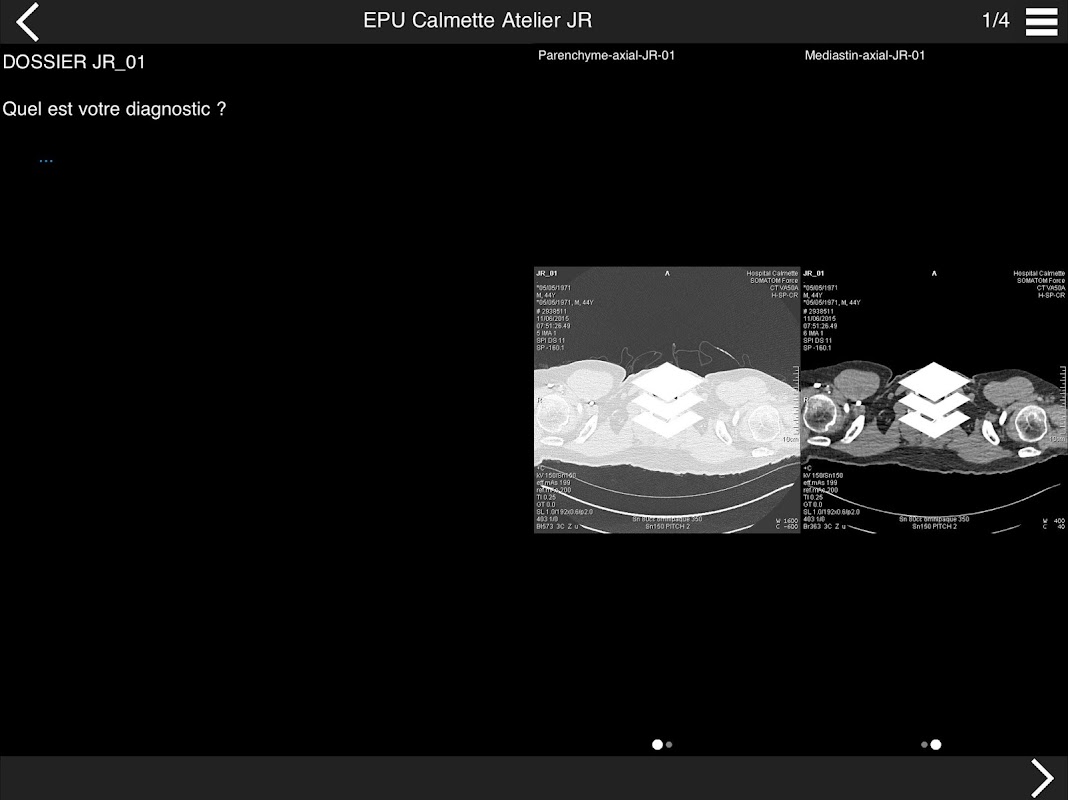

Retrouvez les cas cliniques du Cours intensif de TDM multicoupe du thorax dans cette application.

* Pathologie vasculaire et médiastinale